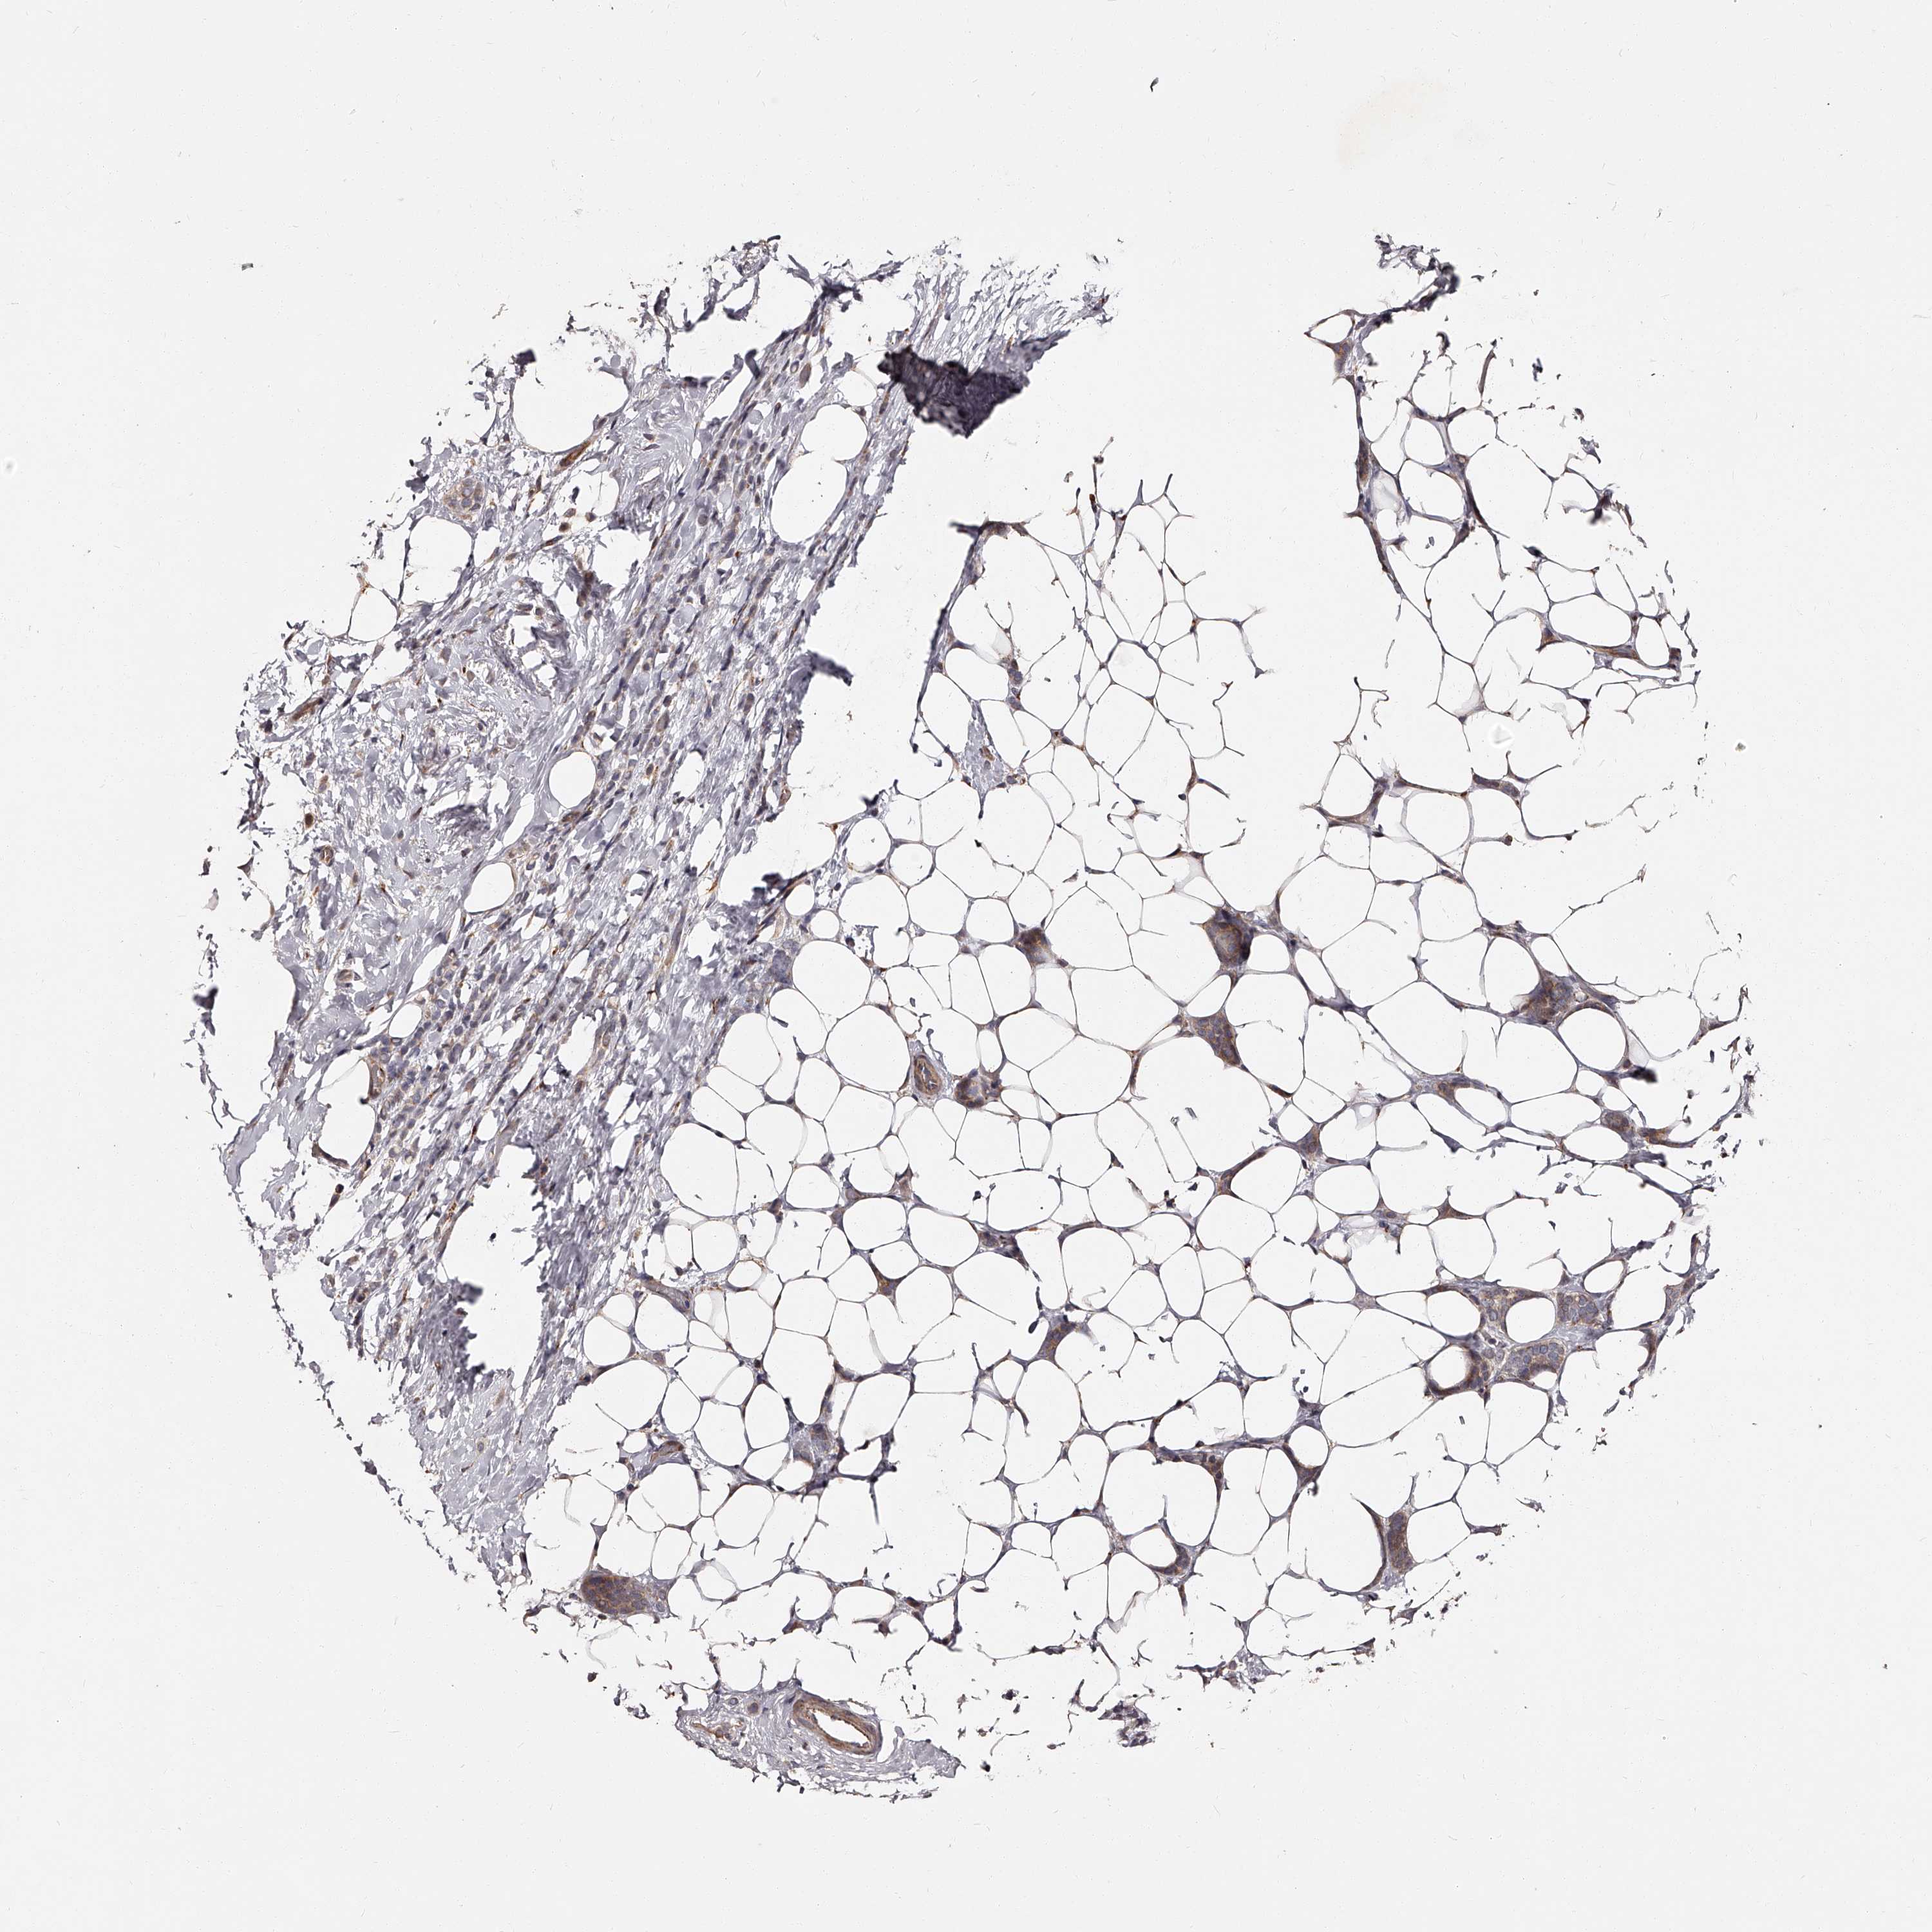

CANCER BREAST CANCER Show tissue menu

BRCA TCGA BRCA VALIDATION PROTEIN EXPRESSION